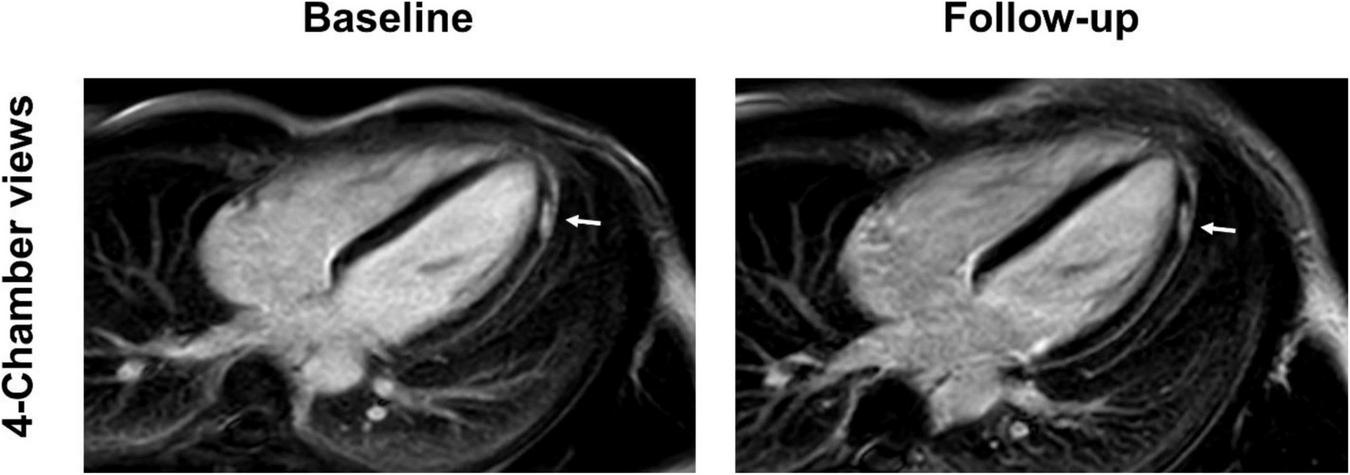

FIGURE 7

4-chamber and short-axis late gadolinium enhancement (LGE) views of a 15-year-old male after receiving the second dose of the Pfizer/BioNTech vaccine. Subepicardial and pericardial LGE at the apical lateral wall (arrows) shows a marked decrease at the 9-month follow-up with residual findings. Resolution of chest pain at follow-up was accompanied by new onset of occasional exertional dyspnea.